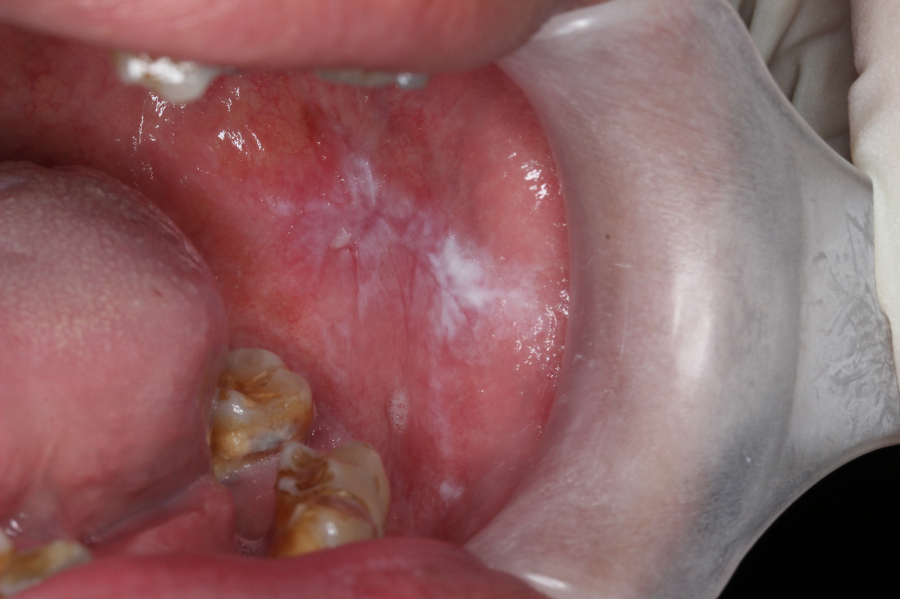

口腔癌初起的表徵很多時是口腔内一些白斑,臨床診斷為口腔白斑病(oral leukoplakia OL) 和口腔類扁平苔蘚黏膜炎(oral lichenoid mucositis OLM)。這些白斑可能在出現一段長時間後才被確診口腔癌,所以能儘早發現並持續監察,防止它們惡化發展至為重要。